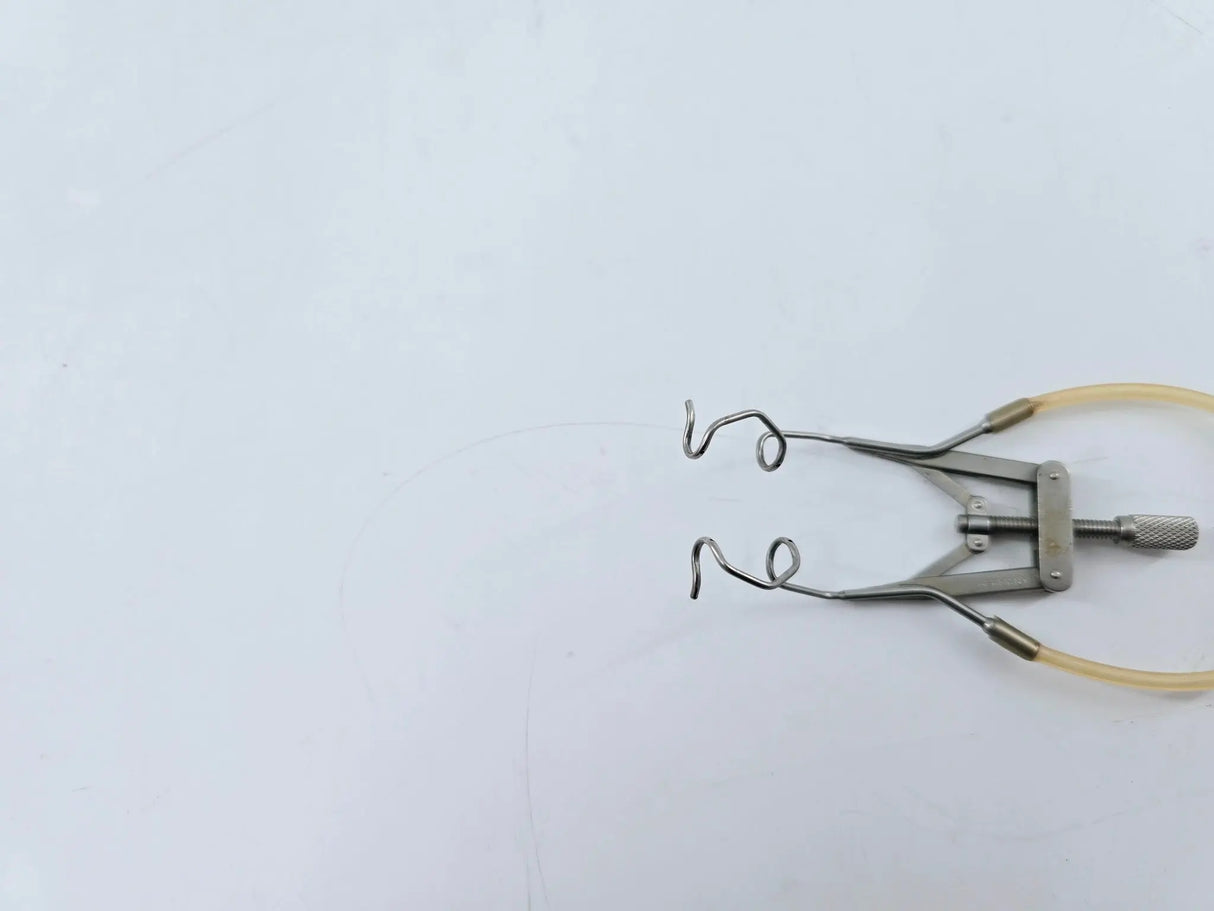

Aspirating Speculum V-Wire, Kratz-Style 3-1/4"

Katena K1-5175 Lieberman Aspirating Speculum V-Wire, Kratz-Style 3-1/4"

For removal of excess fluid from the ocular surface. Supplied with silicone tubing and luer-lock adaptor.

• Model: K1-5175

• Self-Retaining

• Features silicone tubing and luer-lock adapter

• Overall Length (with tubing): 15-1/4 inches